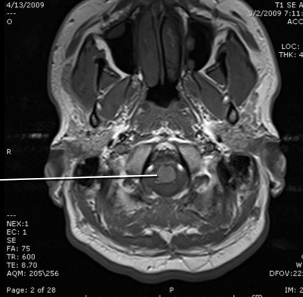

tegmentum of the pons

basis of the pons